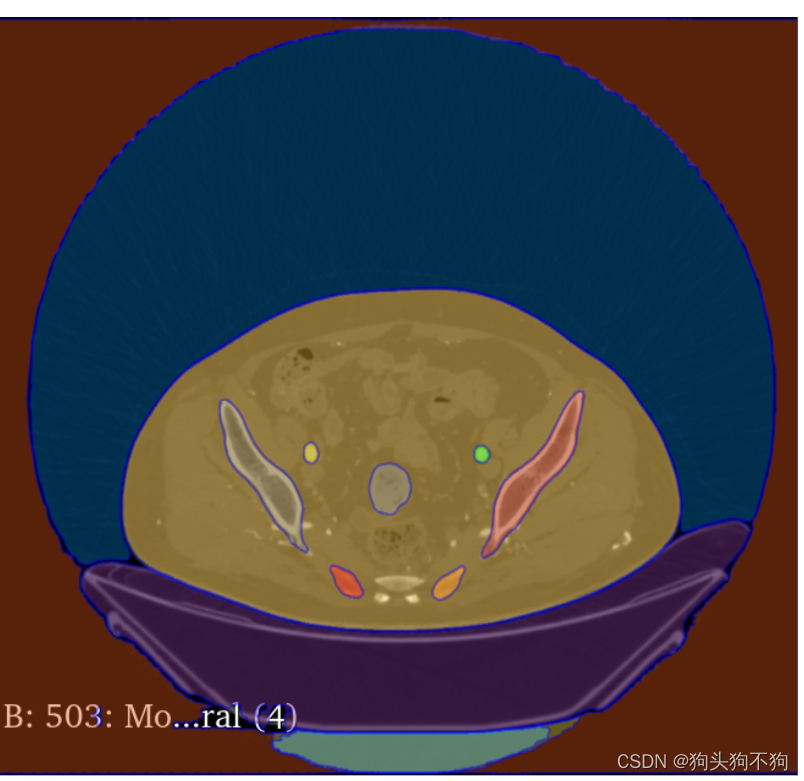

除了网站提供的图像之外,还支持自己上传图像,以人体的CT扫描图像为例

左侧选择栏给了三种模式,点击,框选,和整图分割

整图分割